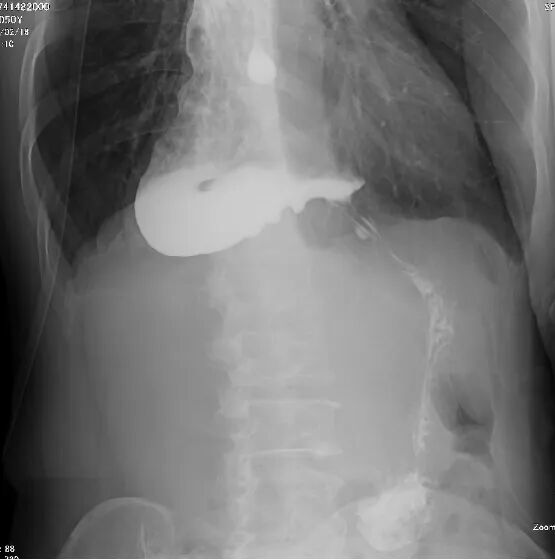

患者收治入院后,医生先后为其完成胃镜、上消化道造影、腹部CT等专科检查。胃镜检查提示,食管下端呈典型“鸟嘴样”改变,胃镜通过困难,食管上段明显扩张;上消化道造影提示,食管下端狭窄呈鸟嘴状,食管整体扩张、蠕动减弱,钡剂通过贲门受阻;腹部CT提示,食管扩张明显,管腔内可见积液积气。

结合症状与影像学检查,患者最终被诊断为贲门失弛缓。针对患者的病情,胃肠外科诊疗团队迅速开展病例讨论,全面评估患者身体状况,制定了个体化微创治疗方案——腹腔镜下贲门肌切开+Dor胃底折叠术,并完善了术前各项准备工作。